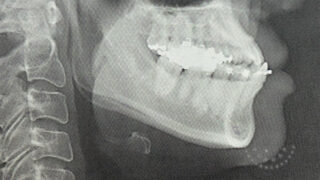

40代から顎変形症治療はじめました#04【顎変形症と診断された】

40代からのだいぶ遅いスタートだけど、治療を始めてよかったと心から思います。現在(2026年1月下旬)は顎変形症の治療(術前矯正)を始めて約5ヶ月経ったところ。矯正器具のついた生活にも少しずつ慣れてきました。前回いろいろな検査を受けて、顎変...